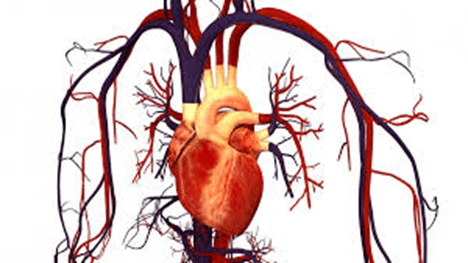

La Organización Mundial de la Salud advirtió que las enfermedades cardiovasculares continúan siendo la principal causa de muerte en el planeta, cobrando más de 18 millones de vidas al año. Expertos señalan que la mayoría de los casos podrían prevenirse si se detectaran a tiempo los factores de riesgo como la hipertensión, el colesterol alto, el tabaquismo y la obesidad.

De acuerdo con nuevos estudios, la acumulación de placa en las arterias (aterosclerosis) comienza desde etapas tempranas de la vida, por lo que los especialistas recomiendan adoptar hábitos saludables desde la juventud: mantener una dieta equilibrada, realizar actividad física diaria, reducir el consumo de sal y evitar el sedentarismo.

La OMS destacó que, si se lograran reducir los factores de riesgo actuales, las muertes por enfermedad cardíaca podrían disminuir hasta en un 80 % para 2050, salvando millones de vidas. Por ello, varios países están promoviendo campañas de prevención y revisiones médicas anuales para detectar alteraciones antes de que aparezcan los síntomas.